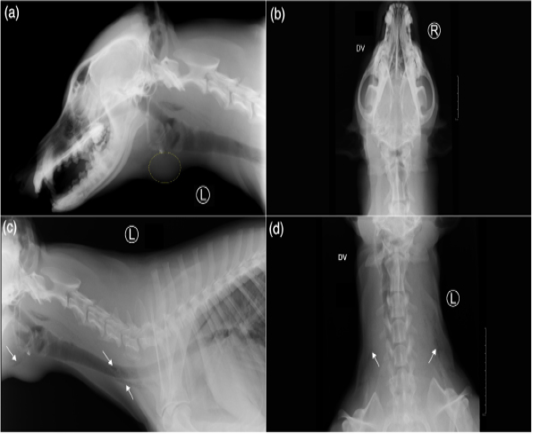

Radiographic views of the skull: left lateral (a) and dorsoventral (b), and the neck: left lateral (c) and dorsoventral (d) of the reported case. (a) There is presence of a rounded soft tissue or fluid opacity structure with distinct margin just ventral to the larynx (marked with yellow dotted circle). (c,d) On both left lateral and dorsoventral radiographs of the neck, multiple small rounded air opacities coalescing to linear gas opacities (white arrows), noticed in bilateral fascial planes of the neck indicating cervical soft tissues emphysema.